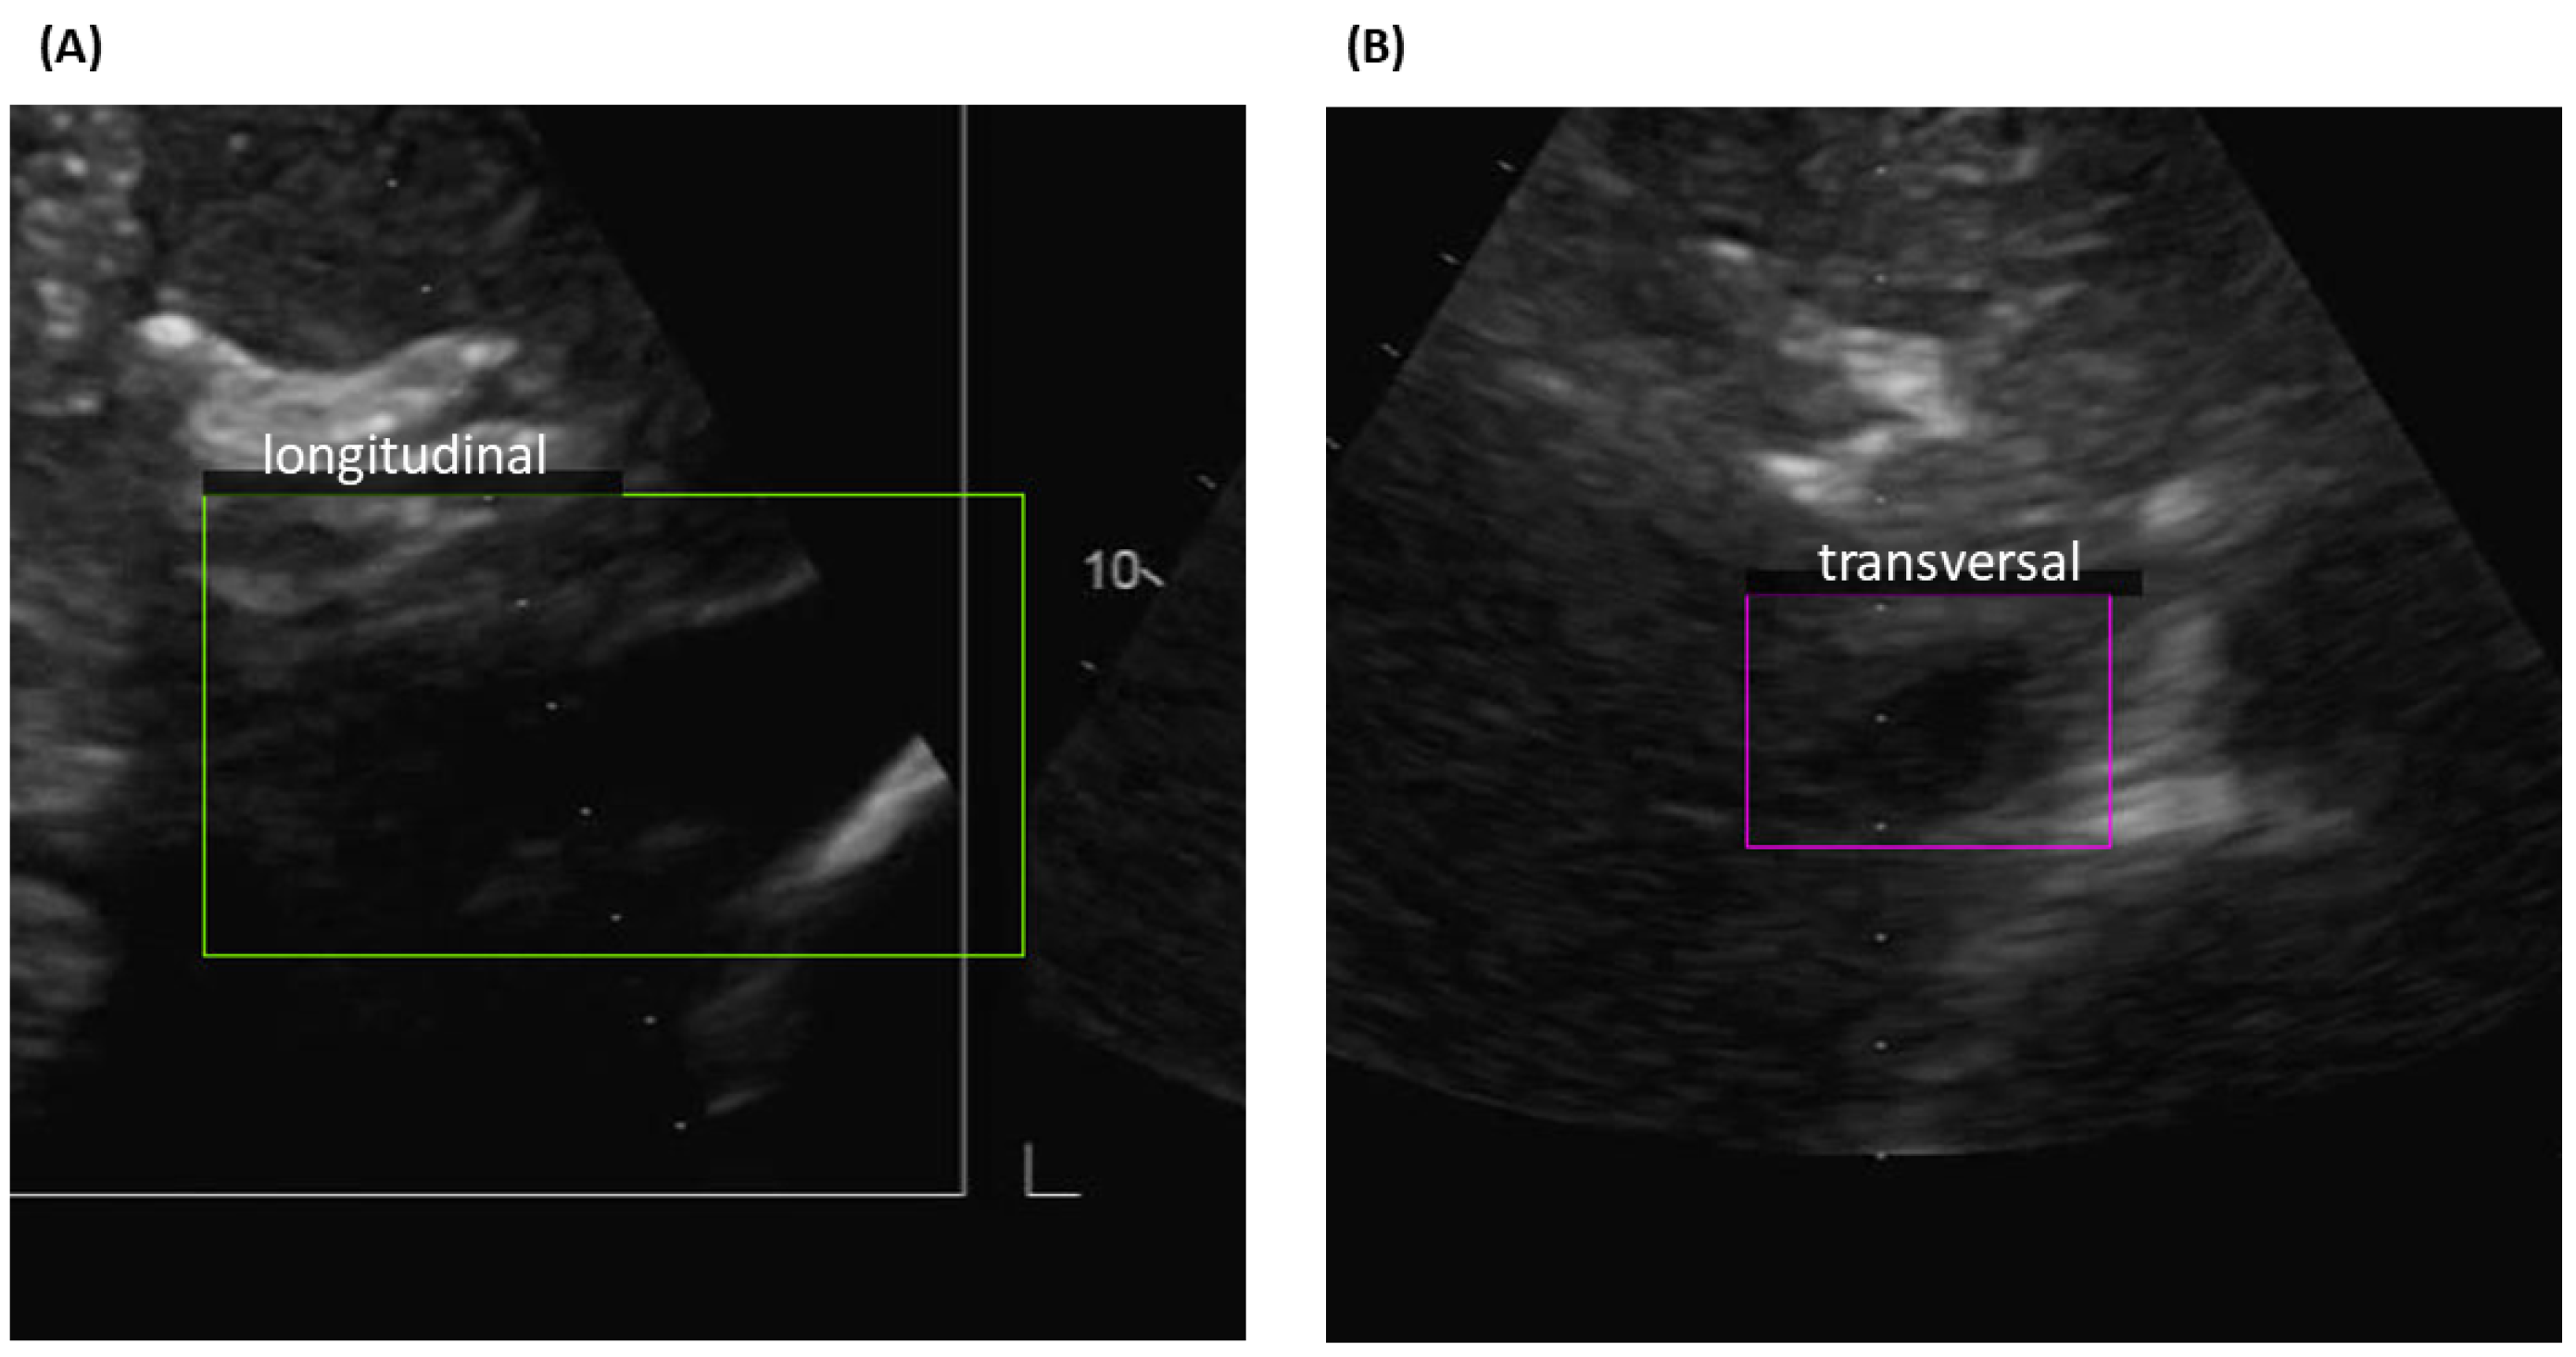

The YOLO networks trained on each of our three datasets were applied to classify the images into two categories, longitudinal or transverse view, and to detect the location of the IVC. An example of IVC detection is shown in Figure 2. The boundaries, green for the longitudinal view and violet for the transversal view, demarcate the regions where the vein is identified. Usually, the position of the vein is around the centre of the frame, but this is not always the case, as shown in the examples reported in Figure 3. YOLO networks examine each box in which the frame is split without having information on its location: thus, there is no bias in detecting the IVC in a specific location.

Figure 3.

Examples of YOLO detection outputs in difficult cases, in which the IVC is not clearly visible. (A) Longitudinal and (B) Transversal view.